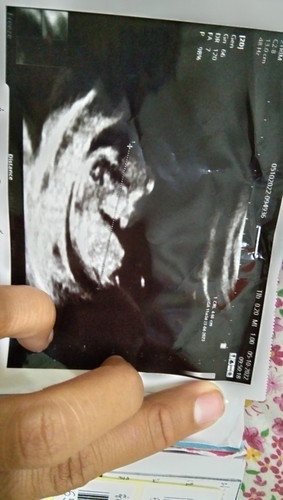

สอบถามเเม่ๆๆค่ะพึ่งท้องได้ 11 สัปดาห์แต่ในใบ sound ขึ้นว่า 11 สัปดาห์กับอีก 3 วันเลยไม่เข้าใจ

คลาดเคลื่อนได้ค่ะ วัดจากหัวลำตัวถึงขาน้อง วัดศีรษะ หน้าท้อง